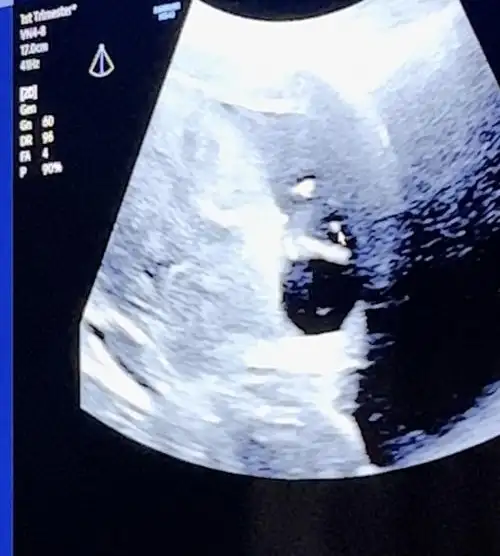

Selam kızlar ben kontrolden geldim her şey yolunda çok şükür burun kemiği ve ense kalınlığı normal yarın nift için kan vercem ☺️ giderken bir kare çikolata yedim beniş o kadar haraketliydi ki o yüzden düzgün bi fotoğrafı yok😂😂 videodan görüntü aldım onu atıyorum. Tahminler kızdı ama doktor bacak arasında çıkıntı gördü resimde okla gösterilen yere bakın 🙈 ilk resimde de eli havada 😍Eki Görüntüle 3242883 Eki Görüntüle 3242884